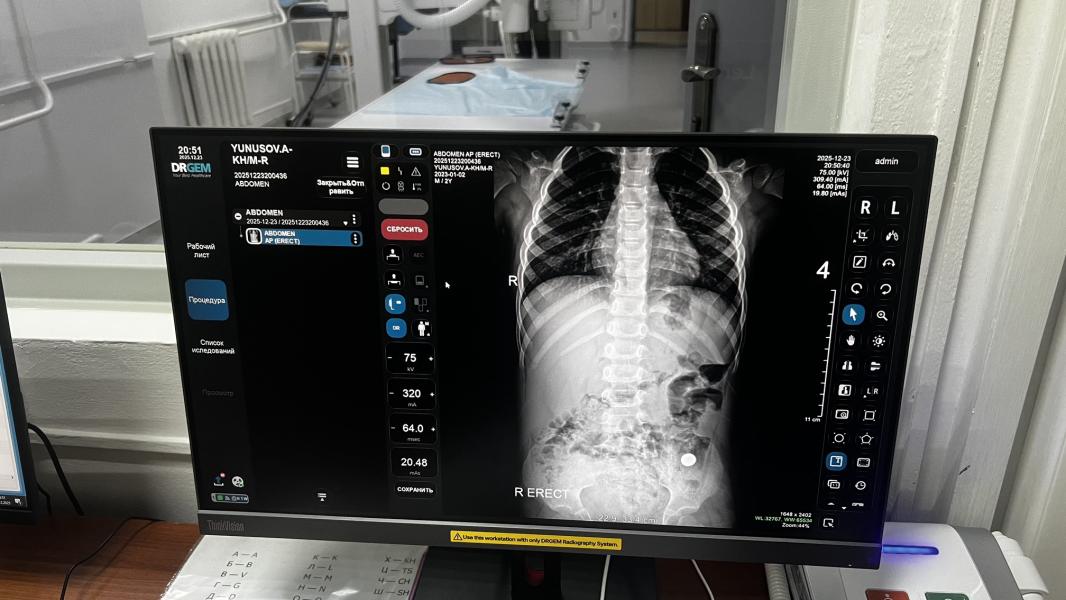

Средний проглотил маленькую батарейку вчера. В первую поехали оттуда отправили во 2 детскую, там сделали рентген и отправили в рдкб , потому что у них нет эндоскописта..

В рдкб сделали повторно рентген и хирург отправив фото эндоскописту вместе сделали вывод что выходит, сказали кормить ребенка и наблюдать до завтрашнего дня. И завтра еще повторно сделать рентген..

Заранее извиняюсь за подробности, но я не нашла в памперсе эту батарейку сегодня.

Кстати ребенок чувствует себя хорошо.